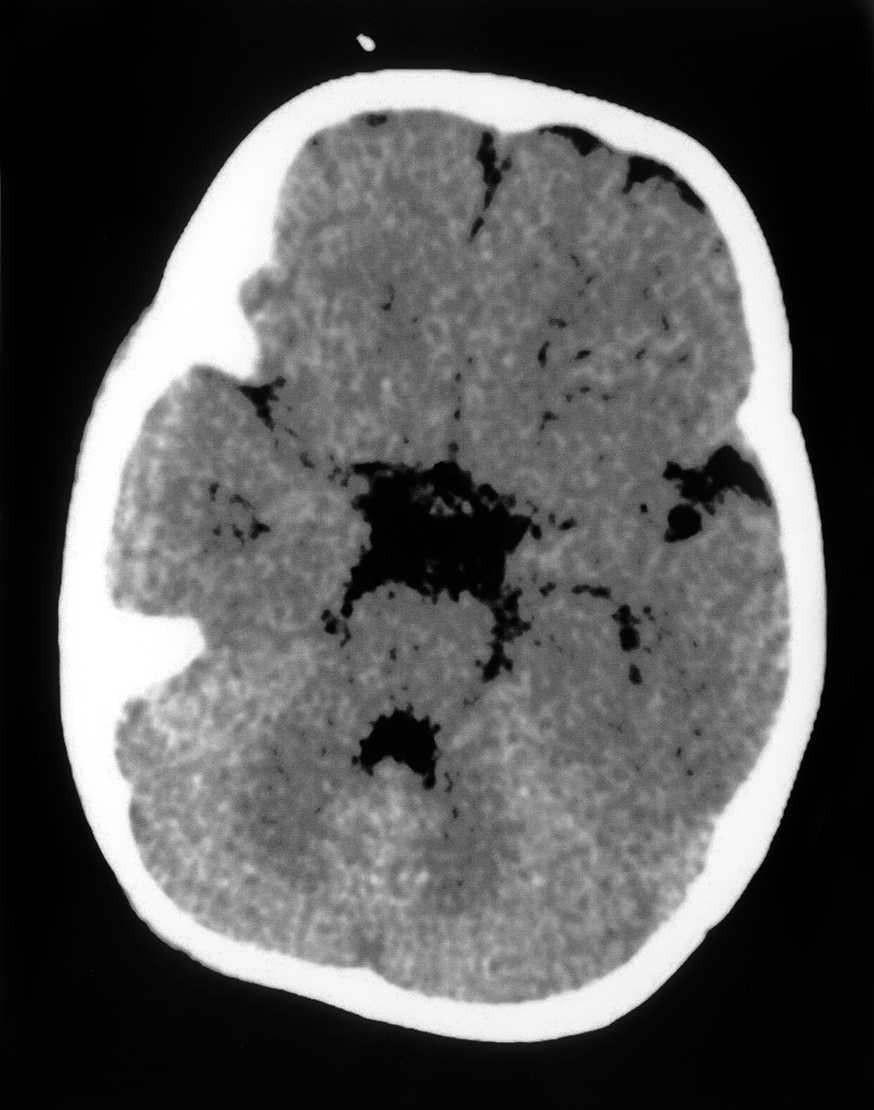

Las exploraciones complementarias realizadas fueron normales: hemograma, bioquímica sérica elemental, creatinfosfocinasa, ácido láctico, piruvato, aminoácidos en suero, ácidos orgánicos en orina, ácidos grasos libres en plasma, carnitina sérica total, carnitina libre, acilcarnitina, cociente acil/libre, equilibrio acidobásico, amonio, hormonas tiroideas, cariotipo, citoquímica de líquido cefalorraquídeo, electromiograma y velocidad de conducción motora de nervio peroneo, biopsia de músculo con estudio estructural, histoquímico y de cuantificación de enzimas de la cadena respiratoria mitocondrial, estudio del ADN mitocondrial de músculo en búsqueda de las mutaciones T8993G, T8993C y A9176C, deleciones únicas o múltiples y depleción por Southern blot, test de edrofonio, estudio de potenciales evocados auditivos del tronco cerebral y una tomografía computarizada (TC) craneal (fig. 1). Se realizaron tres estudios de resonancia magnética (RM) craneal a los 7, 9 y 15 meses de vida que mostraron alteración en la intensidad de la señal en tegmento mesencefálico, pontino y bulbar, más marcado en regiones dorsales (figs. 2 y 3).

Figura 1.TC craneal a nivel del IV ventrículo: ausencia de hallazgos patológicos.

Parece, por lo tanto, claramente definido un subgrupo de pacientes con síndrome de Möbius y riesgo de apnea en los que hay una alta prevalencia de necrosis y/o gliosis junto a calcificaciones del tegmento del tronco, que hasta ahora han sido demostradas mediante TC o necropsia. Este grupo de pacientes representaría los casos con mayor afectación de esta región del rombencéfalo. En el caso que se describe no se encontraron calcificaciones en la TC craneal, pero la RM craneal sí mostró una alteración en la intensidad de la señal en el tegmento paramediano del tronco del encéfalo. Consideramos que la presencia de este hallazgo en la RM craneal de un paciente con síndrome de Möbius puede ser un indicador de riesgo de apnea.